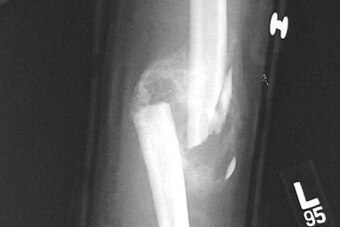

Most clavicle fractures occur in the middle third of the bone, roughly midway between the sternum and shoulder blade. A smaller percentage involves the portion of the clavicle closest to the shoulder, which can complicate treatment. An even smaller fraction occurs near the sternum.

Put together, all of the above likely means Foles' fracture constitutes a minimally displaced midshaft fracture.

Simple midshaft clavicle fractures do not need surgery, and they usually heal quite well with immobilization, rest and time. Additionally, though they may leave a palpable bump in the area of the break, long-term problems usually do not arise.

Certain other types of clavicle fractures do not need surgery as well. As such, it's possible Foles suffered a different type of fracture than a midshaft break. That said, as mentioned, the large majority of fractures involve the middle third of the bone.